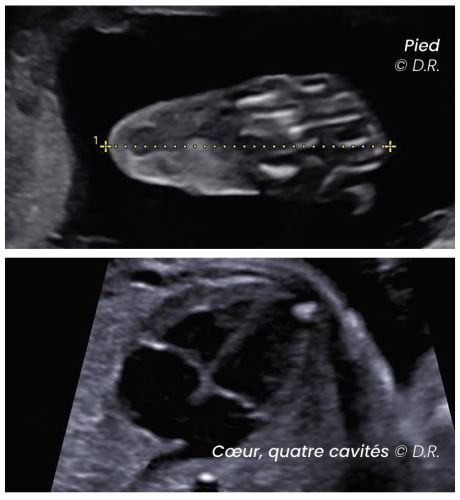

Les discussions qui s’ensuivent parfois, autour du DPNI ou de l’amniocentèse bousculent les patientes. Elles prennent conscience soudain que le ciel n’est pas toujours tout bleu. L’échographie du deuxième trimestre, est la plus complète. C’est là qu’on voit le cœur, le cerveau, les organes du bébé, le placenta, on évalue la croissance…